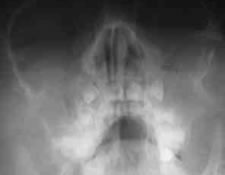

副鼻腔の炎症を診断するには顔のレントゲン検査をいたします。副鼻腔の粘膜はアレルギーの関与が大きいほど肥厚しています。治療には1ヶ月以上かかることもしばしばありますが子供のうちのしっかりと治しておけば、成人に持ち越すことはありません。

▲治療前6歳男児